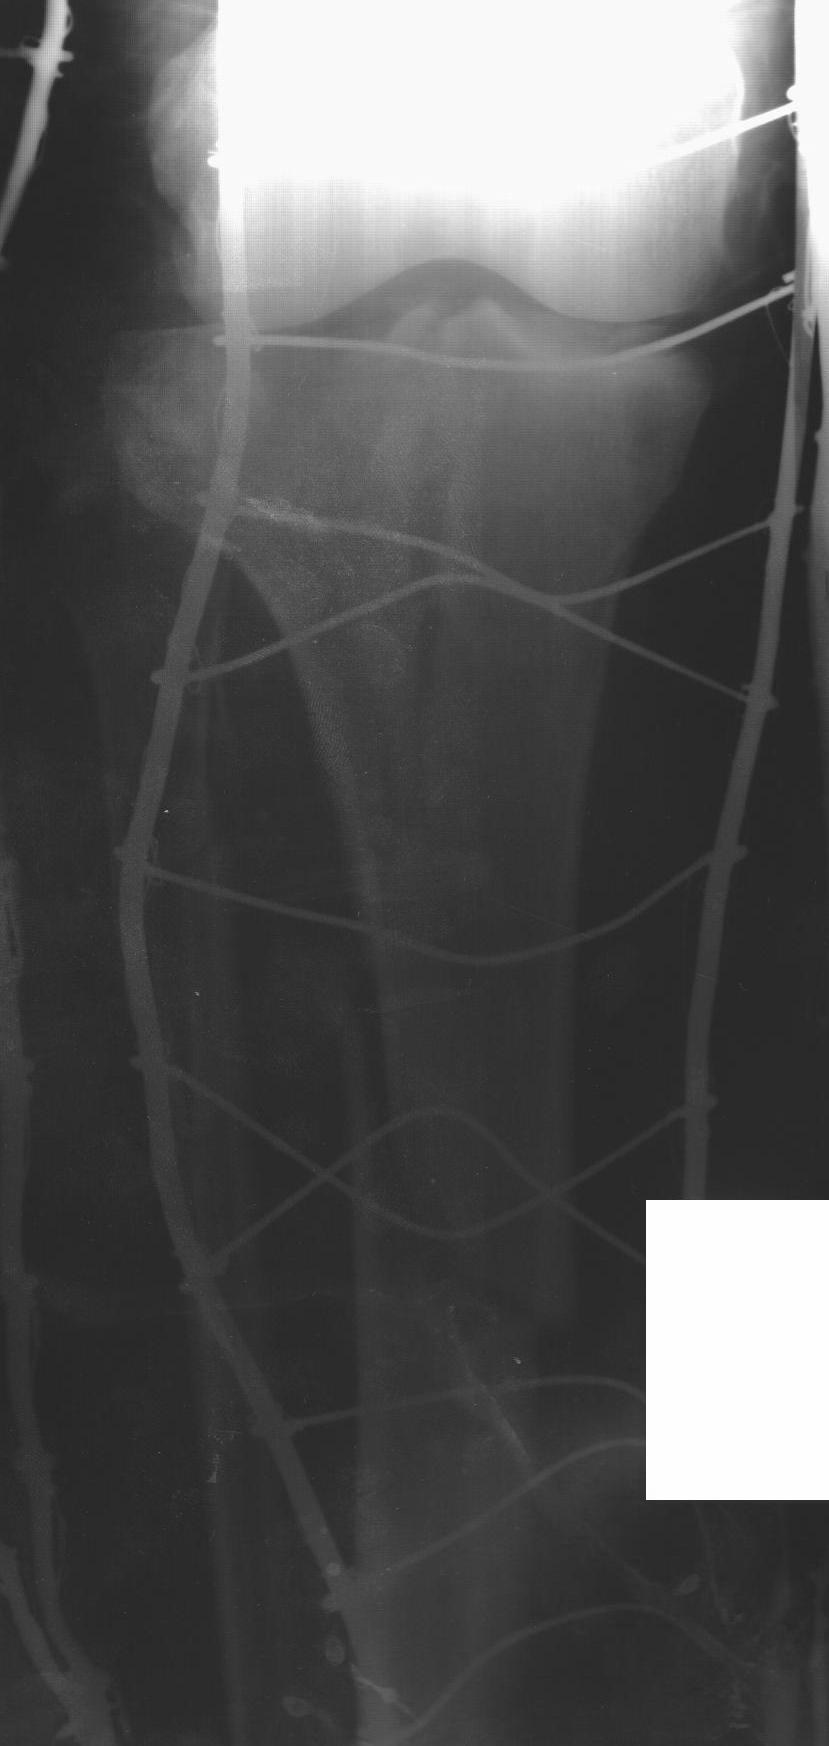

Мужчина 36 л, травму получил 13.12.2010 при падении с высоты (около 2 м), травма изолированная - оскольчатый перелом латерального мыщелка и в/з-с/з диафиза большеберцовой кости. Доставлен в ЛПУ через 30 мин, при поступлении наложено скелетное вытяжение за пяточную кость. На 2-3-и сутки развился выраженный отек в/з-с/з голени, появились сильные боли в голени, парестезии в стопе (компартмент с-м?), консервативно купированы. На данный момент сохраняется выраженный отек голени, боли умеренные, движения в стопе сохранены, пульсация артерии тыла стопы сохранена.

Интересует срок проведения оперативного вмешательства, оптимальный выбор фиксатора (особенно интересует возможность БИОС - мнение А. Н. Челнокова). На месте доступны все основные методы фиксации, ЭОП отсутствует.